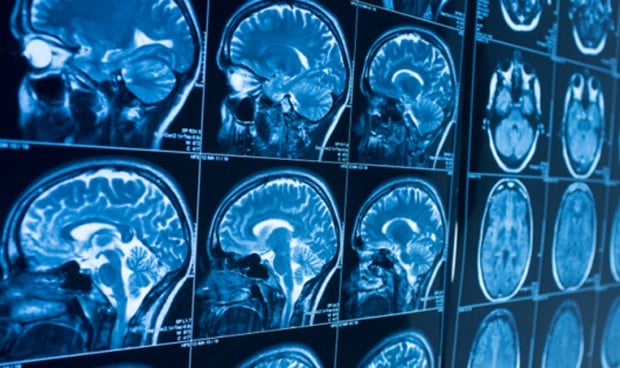

Investigadores de Estados Unidos han identificado, en un estudio multiinstitucional publicado en la revista Radiology, una alta frecuencia de síntomas neurológicos en pacientes con SARS-CoV-2, la enfermedad que provoca el nuevo coronavirus.

Entre los 37 pacientes incluidos, el 76 por ciento se asociaron con un patrón de neuroimagen, el 19 por ciento con dos patrones y el 5 por ciento mostraron tres patrones. Los hallazgos de resonancia magnética más frecuentes fueron: anormalidades de señal ubicadas en el lóbulo temporal medial en el 43 por ciento pacientes, lesiones hiperintensas multifocales de materia blanca no confluentes en Flair y secuencias de difusión, con realce variable, con lesiones hemorrágicas asociadas en el 30 por ciento de los pacientes y microhemorragias de sustancia blanca extensas y aisladas en el 24 por ciento de los pacientes.

Asimismo, el 54 por ciento tenían lesiones hemorrágicas intracerebrales y una presentación clínica más severa. "Se pudieron distinguir tres patrones neurorradiológicos principales, y la presencia de hemorragia se asoció con un peor estado clínico. Se detectó ARN del nuevo coronavirus en el líquido cefalorraquídeo en un solo paciente, y los mecanismos subyacentes de afectación cerebral siguen sin estar claros. Las imágenes y el seguimiento neurológico deben llevarse a cabo para evaluar el pronóstico de estos pacientes", han zanjado los investigadores.